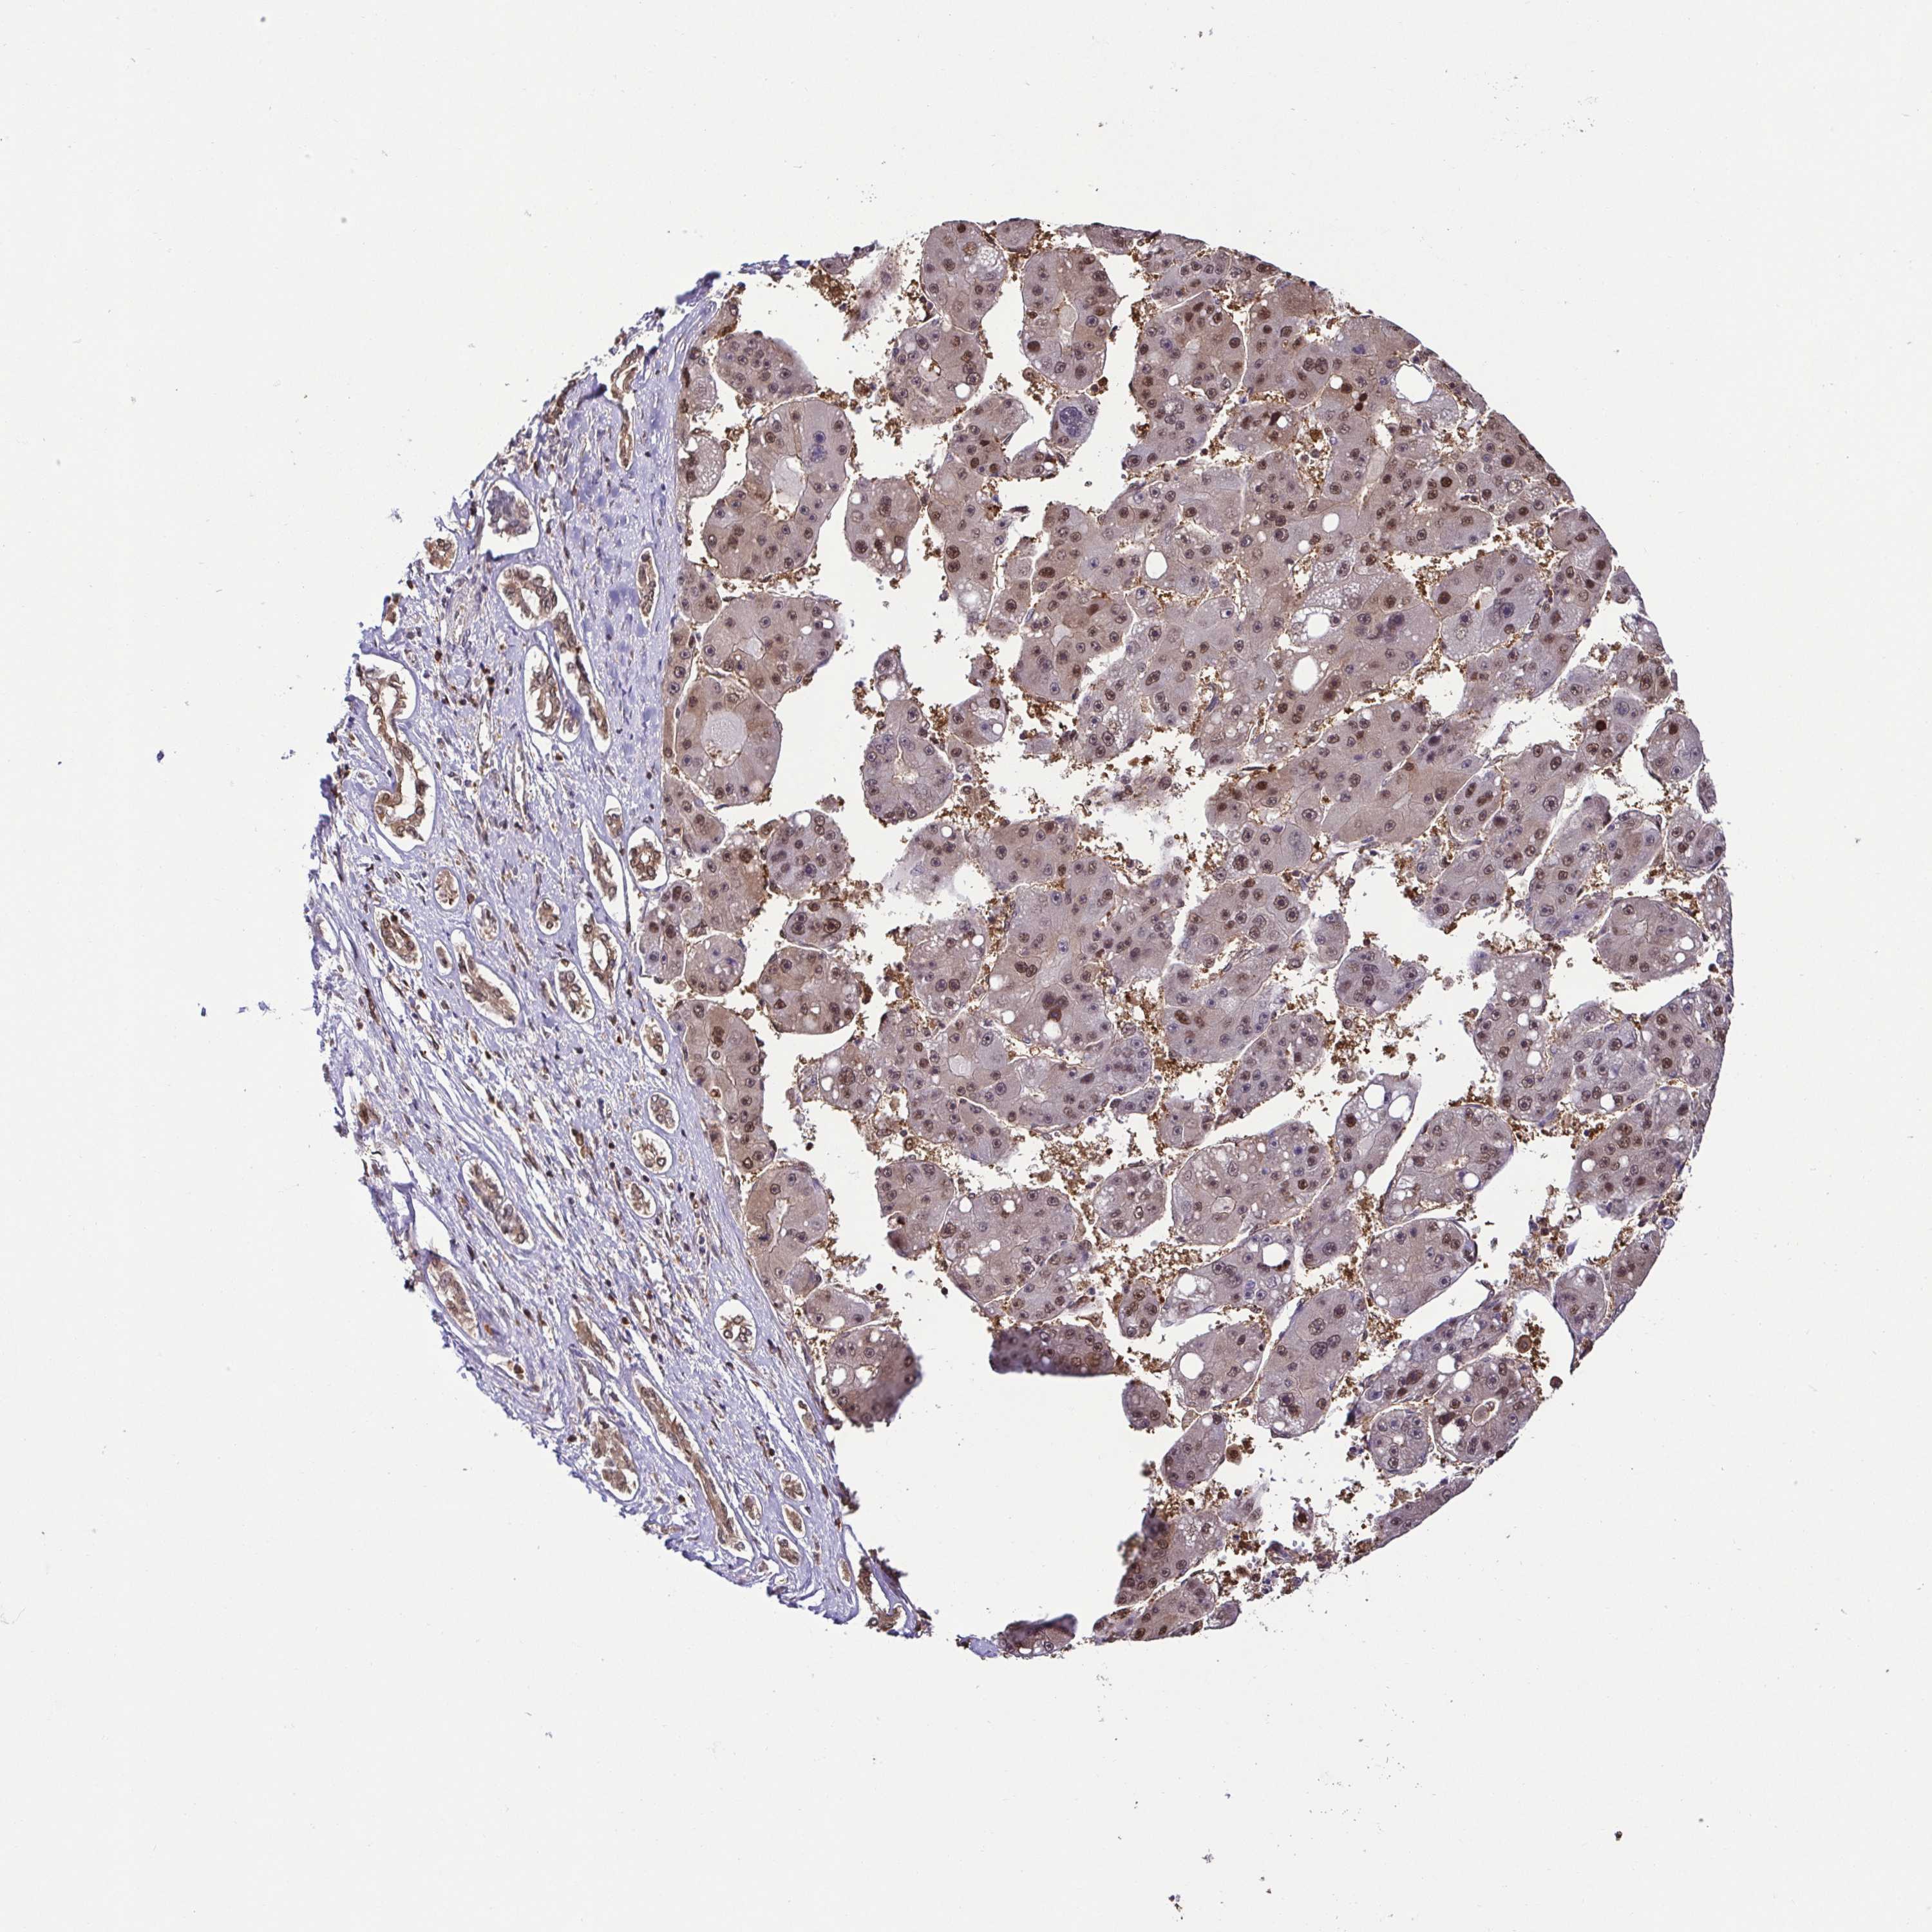

LIVER CANCER - Protein expressioni

A mouse-over function shows sample information and annotation data. Click on an image to view it in a full screen mode. Samples can be filtered based on level of antibody staining by selecting one or several of the following categories: high, medium, low and not detected. The assay and annotation is described here.

Note that samples used for immunohistochemistry by the Human Protein Atlas do not correspond to samples in the TCGA dataset.

Antibody stainingi

Antibody staining in the annotated cell types in the current human tissue is reported as not detected, low, medium, or high, based on conventional immunohistochemistry profiling in selected tissues. This score is based on the combination of the staining intensity and fraction of stained cells.

Each image is clickable and will lead to virtual microscopy that enables deeper exploration of all samples and also displays staining intensity scores, fraction scores and subcellular localization as well as patient and tissue information for each sample.

Antibody HPA053280

Antibody CAB015180

Staining

High

Medium

Low

Not detected

Intensity

Strong

Moderate

Weak

Negative

Quantity

>75%

75%-25%

<25%

None

Location

Nuclear

Cytoplasmic/membranous

Cytoplasmic/membranous,nuclear

Carcinoma, Hepatocellular, NOS

Cholangiocarcinoma